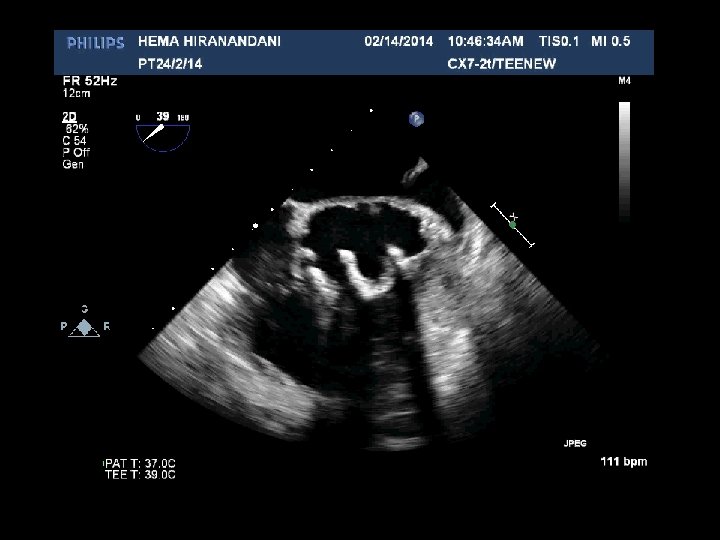

HEMA HIRANANDANI F 57 YRS • • • AVR BIO PROSTHETIC VALVE DEHISCENCE IE MULTIPLE VEGETATIONS ON BIO PRO VALVE AO ROOT ABSCESS SEVERE PARAVALVULAR AR RVSP= 37 mmhg

Hema Hirandani